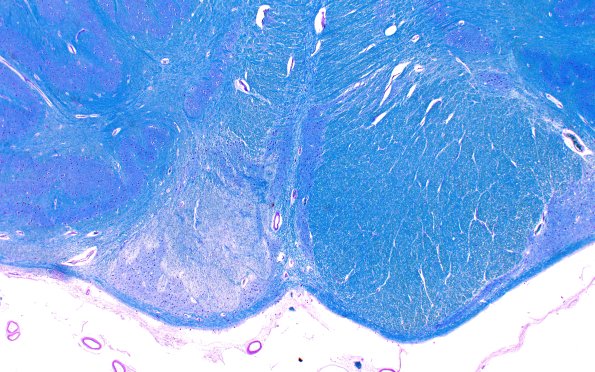

Infarct, Tract Degeneration, illustrative case

2B14D2 Tract Degen (Case 2) N19 2X

Higher magnification of image #2B14D1> (LFB-PAS)